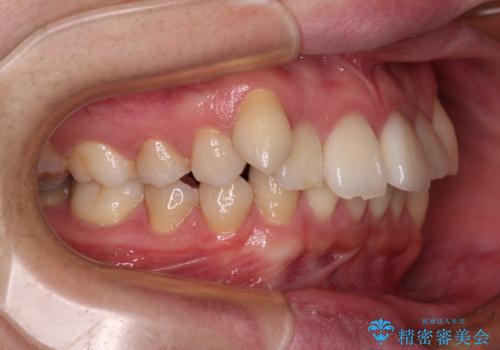

咬み合わせは受け口傾向であり、上顎前歯の叢生が顕著であったことから、第1小臼歯抜歯による矯正治療も検討しましたが、下顎大臼歯を左右ともに抜歯するため、非抜歯による矯正治療を行うこととしました。

矯正治療でインプラント埋入を行い、矯正治療後に気になる前歯と合わせてオールセラミッククラウンによる補綴治療を行うこととしました。

骨造成や歯肉移植など、治癒期間の長い処置を必要としたため治療期間は長くなりましたが、安定した咬み合わせと整った歯列となり、患者様には大変満足していただきました。